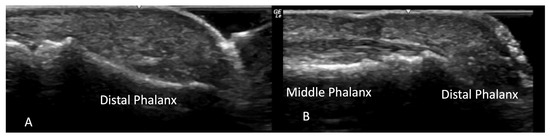

2.1.3. Acro-Osteolysis

4.1. Evaluation of the Fingers

4.1.1. Dorsal Aspect

4.1.2. Volar Aspect